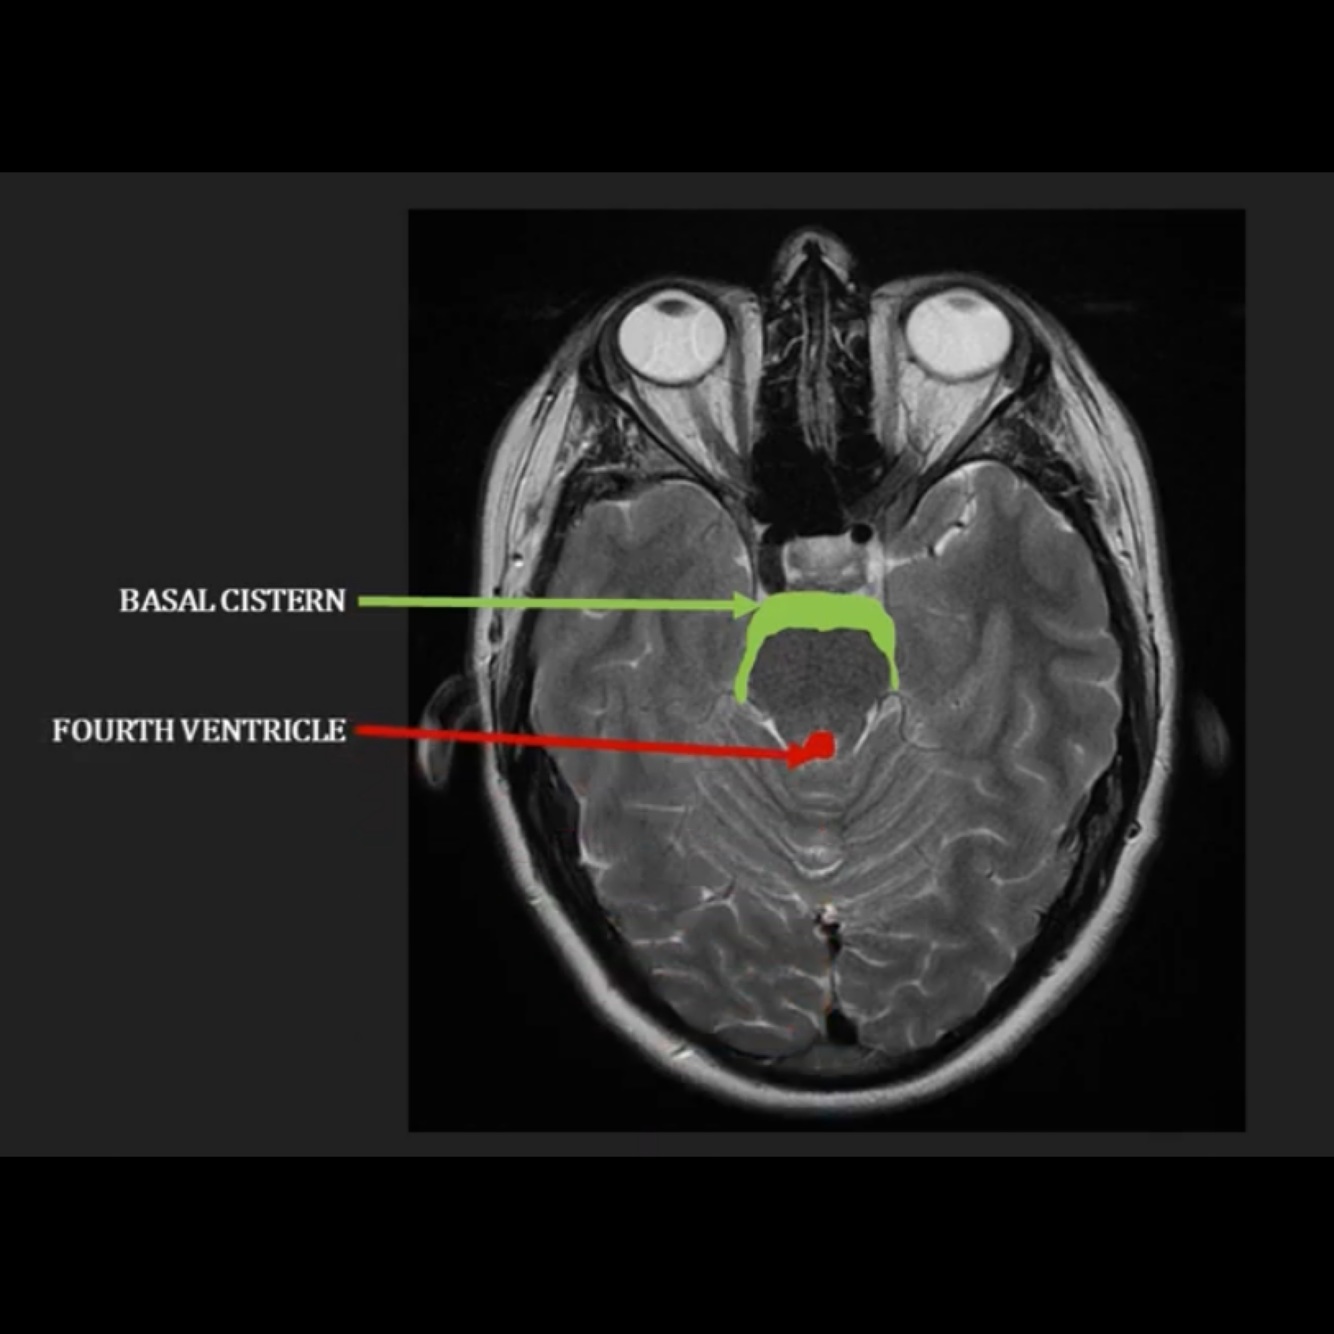

Which structure is filled with CSF and surrounds the brainstem and what is it called, and which structure is the fourth ventricle?

) basal cistern